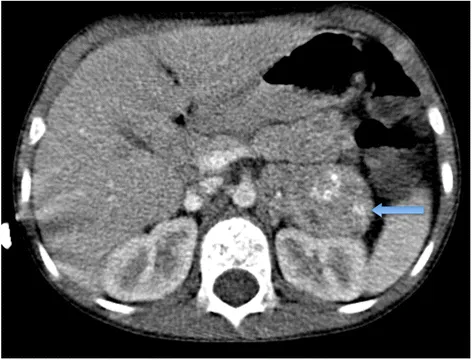

Wilms' Tumor Imaging - Kidney Capers

- Origin: Metanephric blastema; Peak age: 3-4 years.

- Imaging:

- US: Initial, shows intrarenal mass.

ā The 'claw sign' on US/CT, where renal parenchyma is splayed around an intrarenal mass, is characteristic of Wilms' tumor.

- CT: Staging (chest, abdomen, pelvis), contralateral kidney, vascular invasion (renal vein/IVC).

- MRI: Problem-solving (e.g., IVC thrombus extent).

- Features: Well-defined, pseudocapsule; necrosis, hemorrhage common. Typically NO calcification (vs. Neuroblastoma).

- Assess: Contralateral kidney (synchronous tumor/nephroblastomatosis).

- Wilms' tumor: Commonest renal tumor; shows claw sign, respects midline.